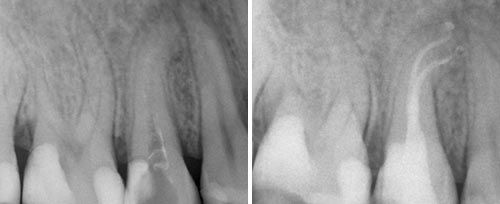

Endodontic Treatment

Courtesy of: Dr. Ralf Schlichting

Laser source: Er:YAG (2940 nm)

Courtesy of: Enrico DiVito, DDS